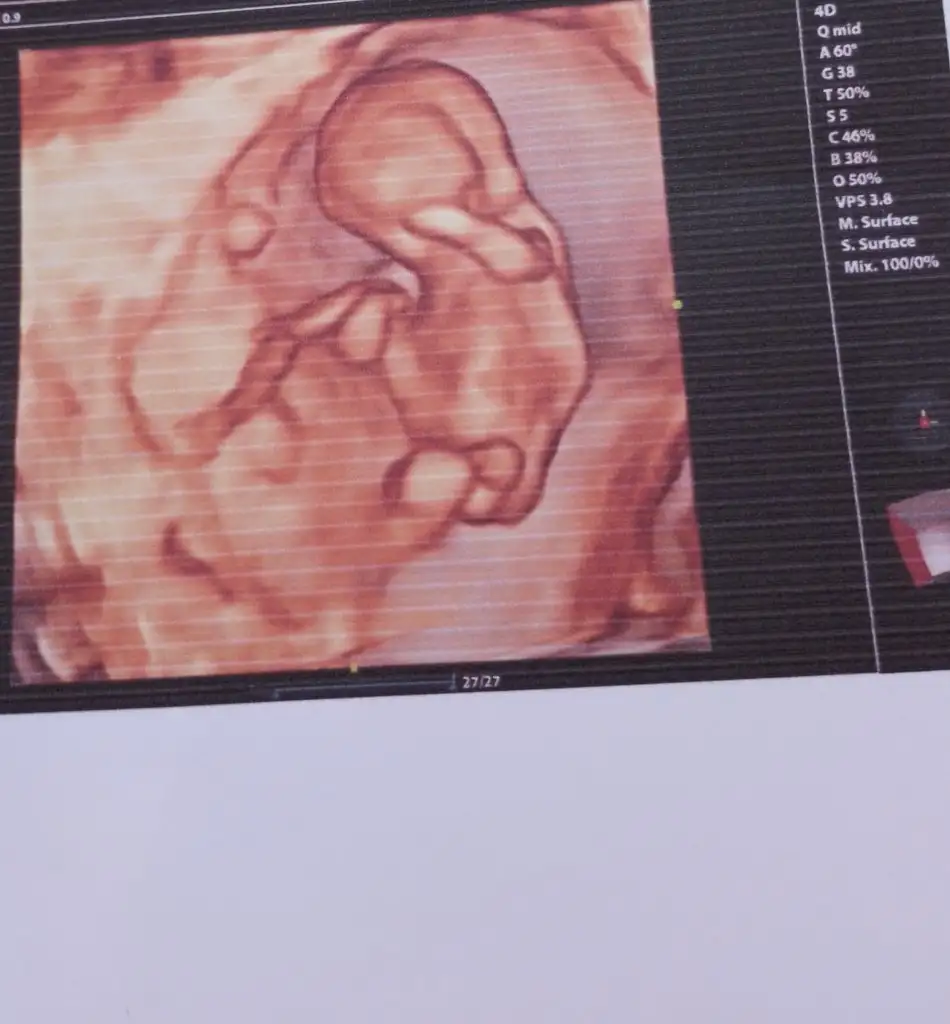

Banada yorum yaparmısınız cok merak edıyorum nub su son kısımda gorunenmı acaba fazla buyuk gıbı anlayamadım

Eklentiler

• Screenshot_2023-11-19-23-36-30-76_965bbf4d18d205f782c6b8409c5773a4.webp

12,4 KB · Görüntüleme: 94